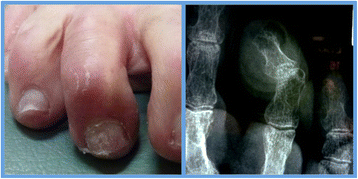

Complex digital deformity included simple digital deformity with the addition of metatarsophalangeal joint (MTPJ) contracture resulting in subluxation or dislocation at that level (Figure 2). Surgical procedures in this group involved those described for simple deformity as well as percutaneous reconstructive procedures at the metatarsophalangeal joint level. Examples include distal metatarsal osteotomies and soft tissue releases at the MTPJ.

Figure 2

Complex digital deformity (pre-operative). Crossover 2nd toe deformity with subluxation at the MTPJ as seen clinically and radiographically. Note the concomitant hallux valgus deformity.